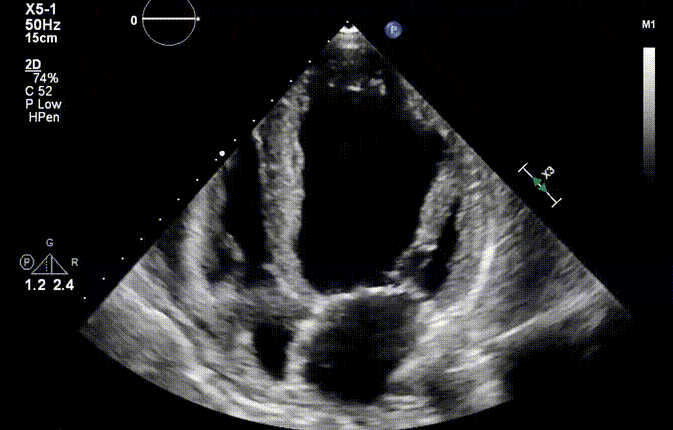

The following cardiac image gallery covers standard views and common life threatening conditions relevant to the practice of Anesthesiology